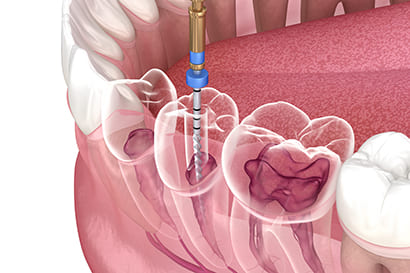

2.マイクロスコープによる精密根管治療(マイクロエンド)

マイクロエンドとはマイクロスコープを使用した精密な根管治療です。

マイクロスコープは20倍以上拡大でき肉眼では見えない箇所まで見える状態で治療ができるので、精密な根管治療を可能とします。

より良い治療の結果を求めるのであれば、マイクロエンドは必須といえるでしょう。

抜歯を宣告された方はマイクロエンドで歯を残すことができるかもしれません。

3.マイクロスコープによるMTAセメント根充

マイクロスコープにより感染物質を除去後の空洞には、MTAと言う歯科用セメントを使用して根充します。またこの根充の時もマイクロスコープを使用することが精密さを増します。

根管治療では根管内の感染物質を除去したら、根管内に薬剤をすき間なく埋める「根管充填」を行います。

根管治療の成功率をあげるためには、マイクロスコープを用いてより慎重に精密に「根管充填」をする必要があります。

このときの根管充填で「MTAセメント」を使用することがポイントです。